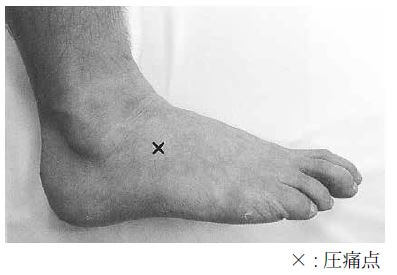

問題105.34歳の男性。バレーボールの練習中、ジャンプでつま先から着地し足部を捻り来所した。足背部外側の腫脹と疼痛を訴える。受傷時の肢位を強制すると写真に示す部位の疼痛が増強し、同部に圧痛を認める。足関節の前方引き出し症状はない。写真を下に示す。

解答2

解説

・34歳の男性。

・バレーボール中:ジャンプでつま先から着地し足部を捻った。

・足背部外側の腫脹と疼痛を訴える。

・受傷時の肢位を強制すると疼痛が増強し、同部に圧痛あり。

・足関節の前方引き出し症状はない。

→ほかの選択肢が消去できる理由も上げられるようにしよう。

2.〇 正しい。二分靱帯損傷が最も考えられる損傷である。なぜなら、本症例の症状と一致するため。踵立方関節背側に疼痛が出ることが特徴である。

・二分靱帯とは、縦足弓の外側部を支持するY靭帯のことである。他にも外側の踵骨・立方骨・舟状骨を硬く締結する。つま先立ちやジャンプの着地で内反捻挫をした際に損傷を受ける。